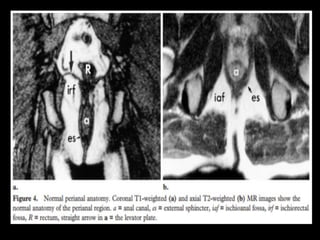

a = anal canal, IAF = ischioanal fossa, IRF = ischiorectal fossa, R = rectum

Line diagram shows the normal anatomy of the perianal region in the

• MR Imaging of Perianal Fistulas Normal Anatomy

The anatomy of the perianal region is well

demonstrated on coronal and axial MR images

(Fig 4).

• The internal and external sphincters are not

separately resolved in normal subjects on MR

images obtained with a body coil,

but the sphincter complex, ischiorectal fossae,

and levator ani sling are clearly seen.